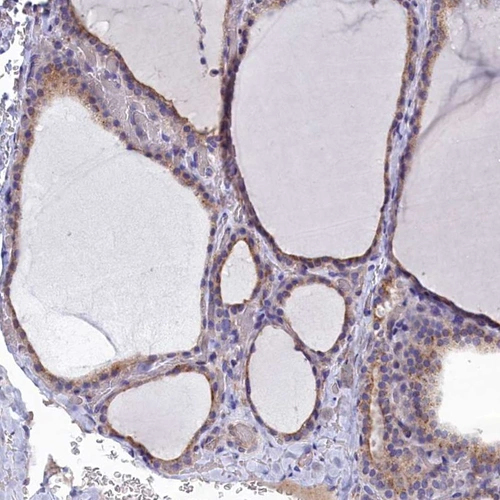

Immunohistochemical staining of human thyroid gland shows moderate cytoplasmic positivity in glandular cells.